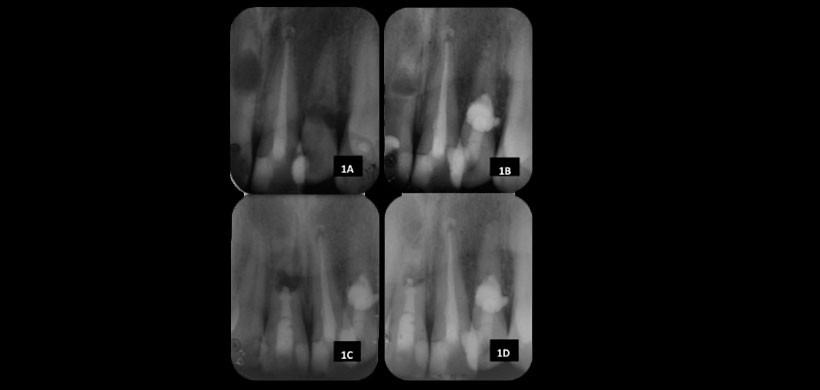

Figura 1: A) Radiografía preoperatoria; B) Revisión de un año de la pieza  22; C) Postoperatorio del diente 11 lleno de MTA; D) Nueve meses de revisión después de la cirugía del diente 11